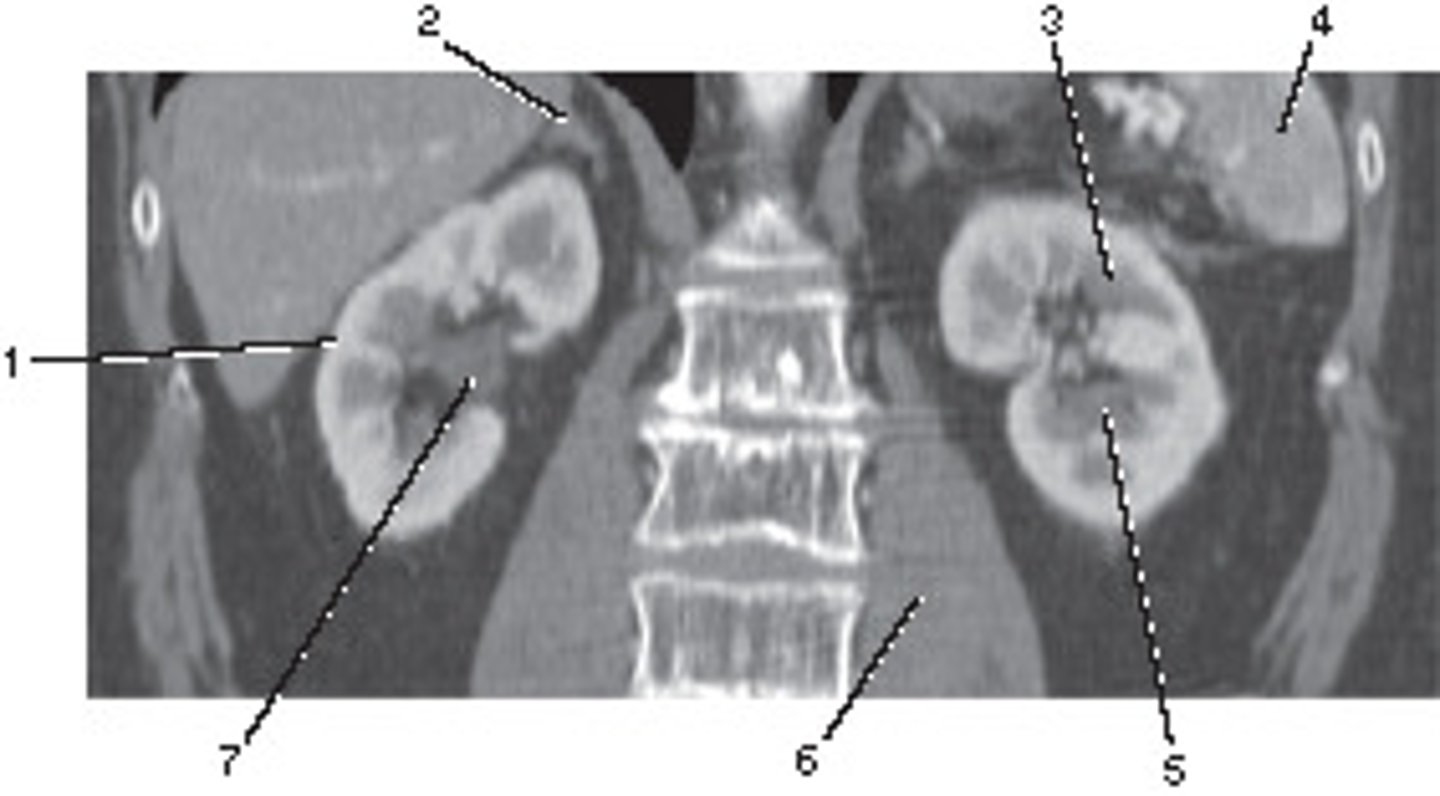

Corticomedullary;

30-40 seconds after injection,

the corticomedullary phase demonstrates optimal enhancement of the renal cortex with maximum differentiation from the renal medulla

This image of the abdomen was most likely acquired in which in which renal enhancement phase?

<p>This image of the abdomen was most likely acquired in which in which renal enhancement phase?</p>

Renal Cortex

Number 1 corresponds to which of the following?

<p>Number 1 corresponds to which of the following?</p>